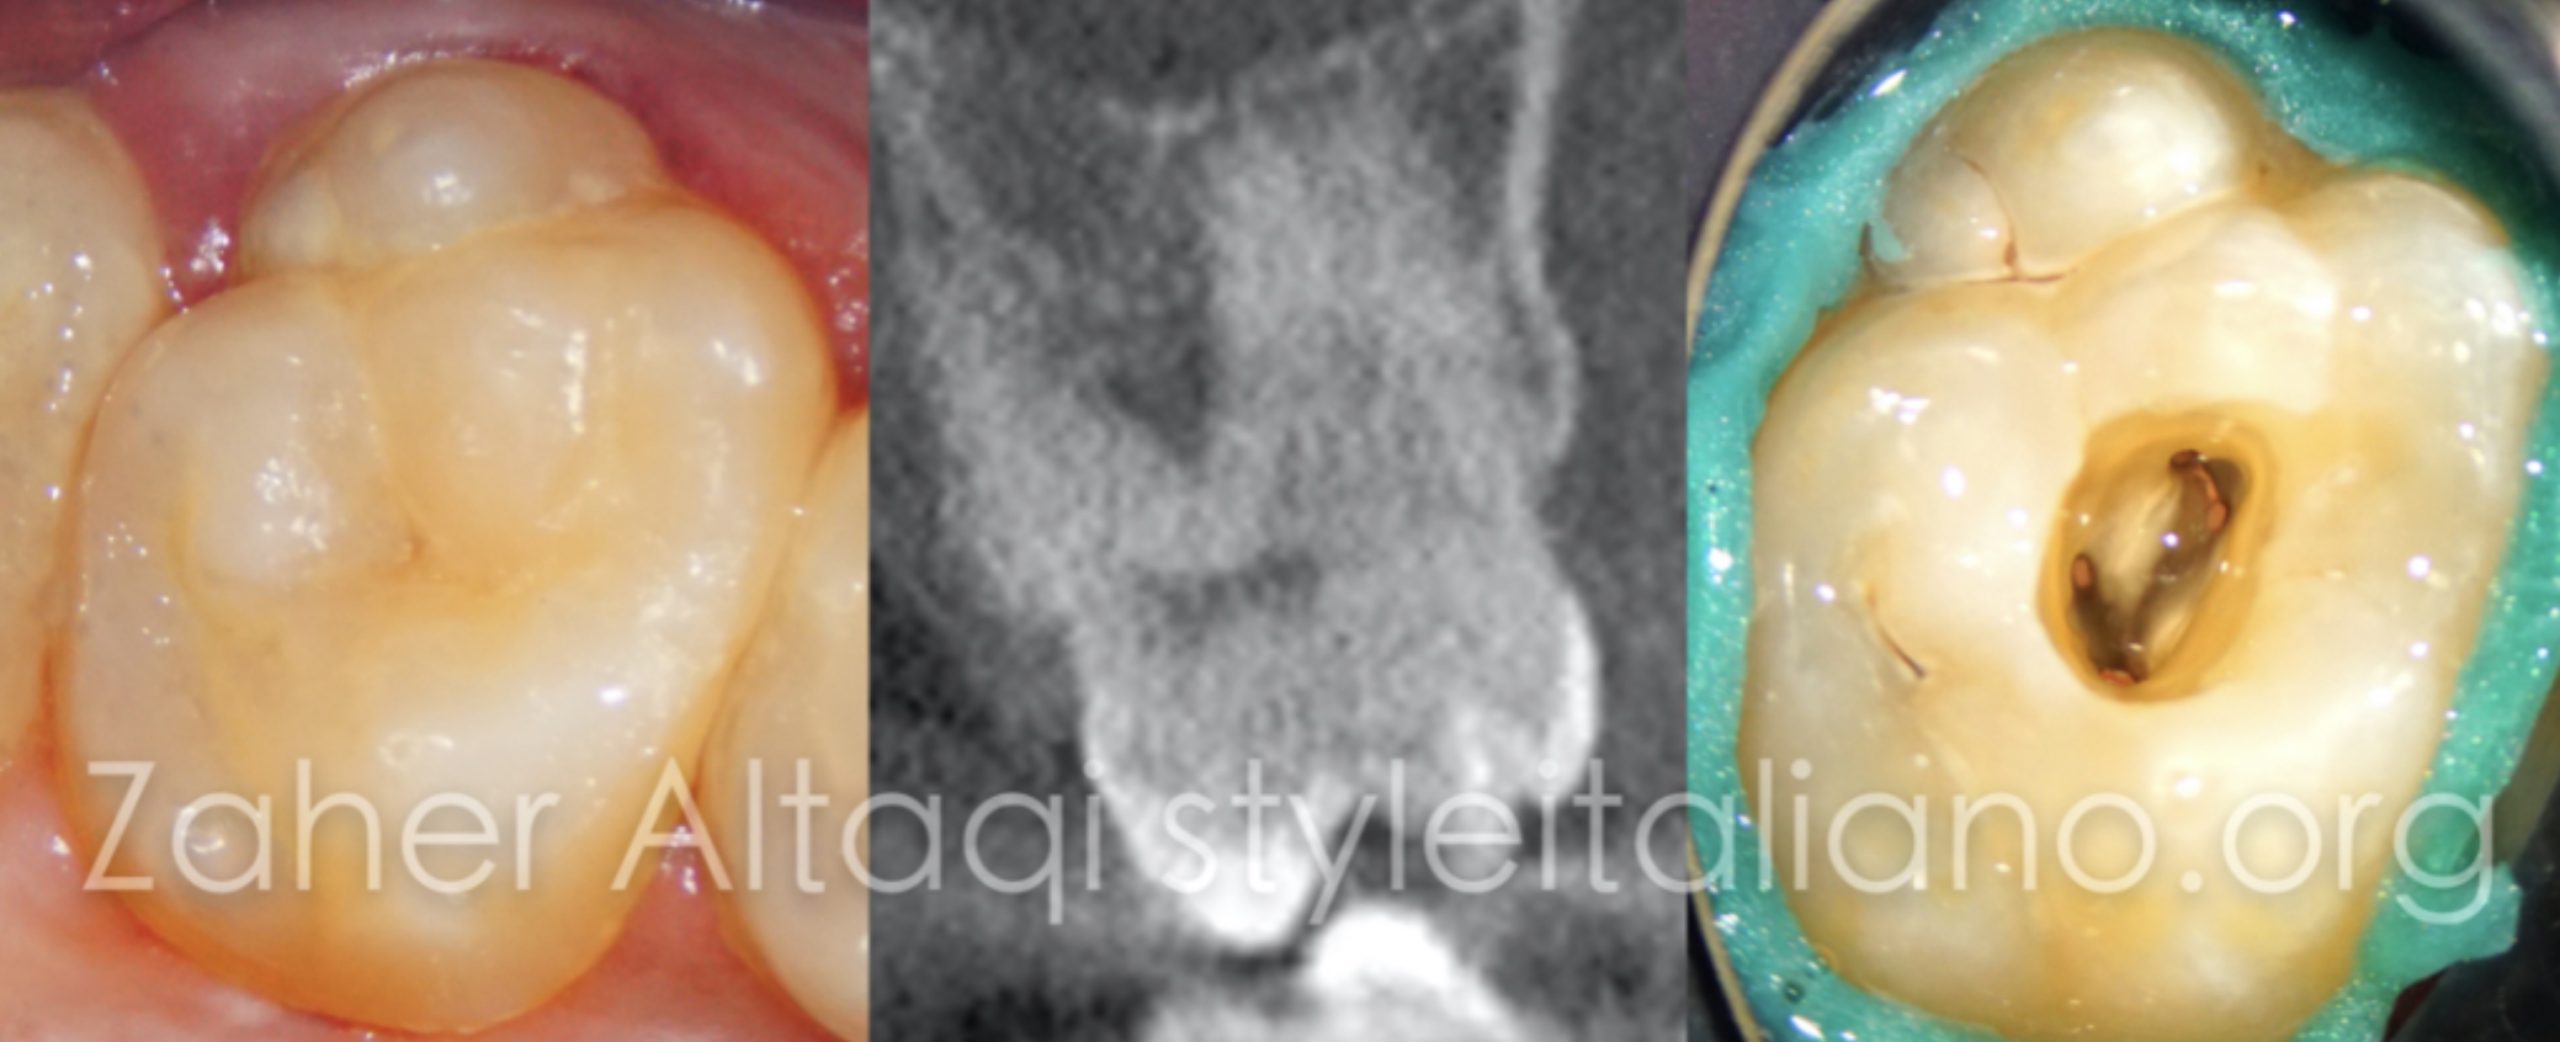

Dens invaginatus

Dens invaginatus

Dens invaginatus is malformation of teeth probably resulting from an infolding of the dental papilla during tooth development. Affected teeth show a deep infolding of enamel and dentine starting from the foramen coecum or even the tip of the cusps, and which may extend deep into the root. Teeth most affected are maxillary lateral incisors and bilateral occurrence is not uncommon. The malformation shows a broad spectrum of morphologic variations and frequently results in early pulp necrosis. Root canal therapy may present severe problems because of the complex anatomy of the teeth.